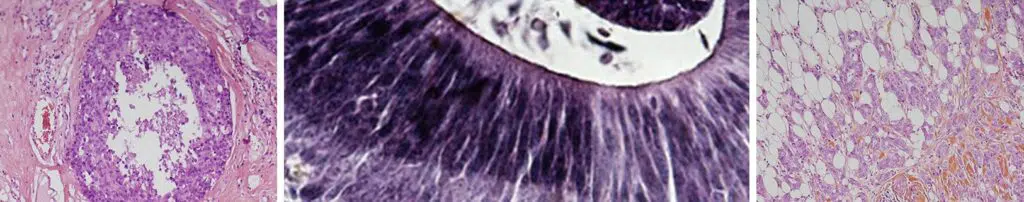

الخزعة

الخزعة هي إجراء يتم فيه أخذ عينة من النسيج المشبوه باستخدام إبرة، وذلك تحت التخدير الموضعي. يتم إجراؤها غالبًا من قبل طبيب الأشعة.

الخزعة وتحليل العينة تحت المجهر هما الطريقتان الوحيدتان اللتان تسمحان بتأكيد أو استبعاد تشخيص الآفة المشبوهة. في حالة السرطان، يسمح الفحص التشريحي المرضي بتحديد نوع الورم وخصائصه.

- الخزعة الدقيقة تُجرى باستخدام إبرة رفيعة تحت التخدير الموضعي، وتُستخدم لأخذ عينة صغيرة من الآفة.

- الخزعة الكبيرة تُجرى باستخدام إبرة أكبر قليلًا، مما يسمح بأخذ عينات أكبر وأكثر عددًا، وغالبًا ما تُستخدم في حالة وجود بؤر تكلسات دقيقة.

يمكن أن تكون الخزعة موجهة إما بواسطة الموجات فوق الصوتية (في هذه الحالة، تُسمى الخزعة الموجهة بالموجات فوق الصوتية) أو بواسطة التصوير الشعاعي للثدي (الخزعة الستيريوتكسيّة). وفي حالات نادرة، يمكن توجيهها بواسطة التصوير بالرنين المغناطيسي.

هناك أيضًا تقنية أخرى تُسمى البزل الخلوي، وهي تُستخدم عادة لفحص العقد الليمفاوية، حيث يتم أخذ بضع خلايا باستخدام إبرة دقيقة جدًا.

في بعض الحالات، يتم وضع مشبك صغير في المنطقة التي تم أخذ الخزعة منها، ليكون بمثابة علامة للمراحل اللاحقة من العلاج.